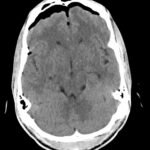

Tension pneumocephalus is a rare neurosurgical emergency requiring cranial decompression to prevent permanent neurological injury, herniation, and death. In this report, we present a trauma patient struck by a knife in the forehead who presented with agitation and vomiting. Imaging ultimately revealed a minimally displaced frontal sinus fracture through both the anterior and posterior walls of the sinus. This disruption, acting as a ball-valve for air entry into the cranium, resulted in extensive pneumocephalus and eventual tension physiology. The patient required immediate neurosurgical decompression. This case illustrates both the importance in recognition of this uncommon pathology as well as the need for rapid reassessment with clinical changes in trauma patients.